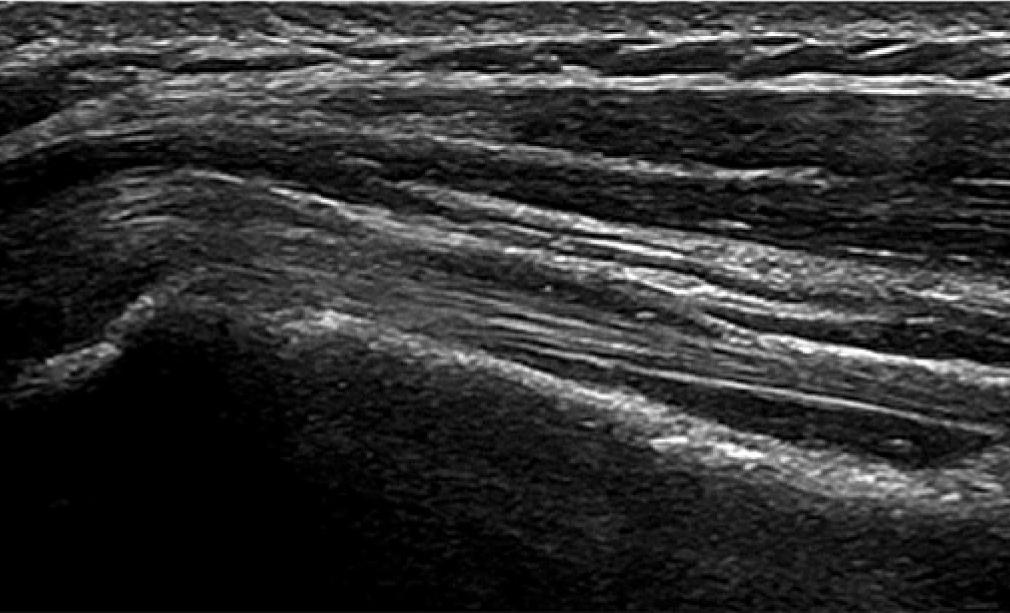

The bursa should be seen as three parallel stripes. The top and bottom should be of high echogenicity compared to the low central stripe (Fig. 1). If the lower stripe is not seen, then this would imply a bursal surface supraspinatus or infraspinatus fraying (Fig. 2). If the stripes are not clear in outline, appearing blurred, then the presence of an adhesive bursitis should be considered (Fig. 3). In a child or young adult, the central stripe may be very thin, and the bursa may appear as one stripe if the resolution of the ultrasound machine is poor.

The 3 distinct stripes of the subdeltoid subacromial bursa are seen here

The upper layer of the supraspinatus tendon is missing

The subdeltoid subacromial bursa is not as distinct on the right of the image compared to the left